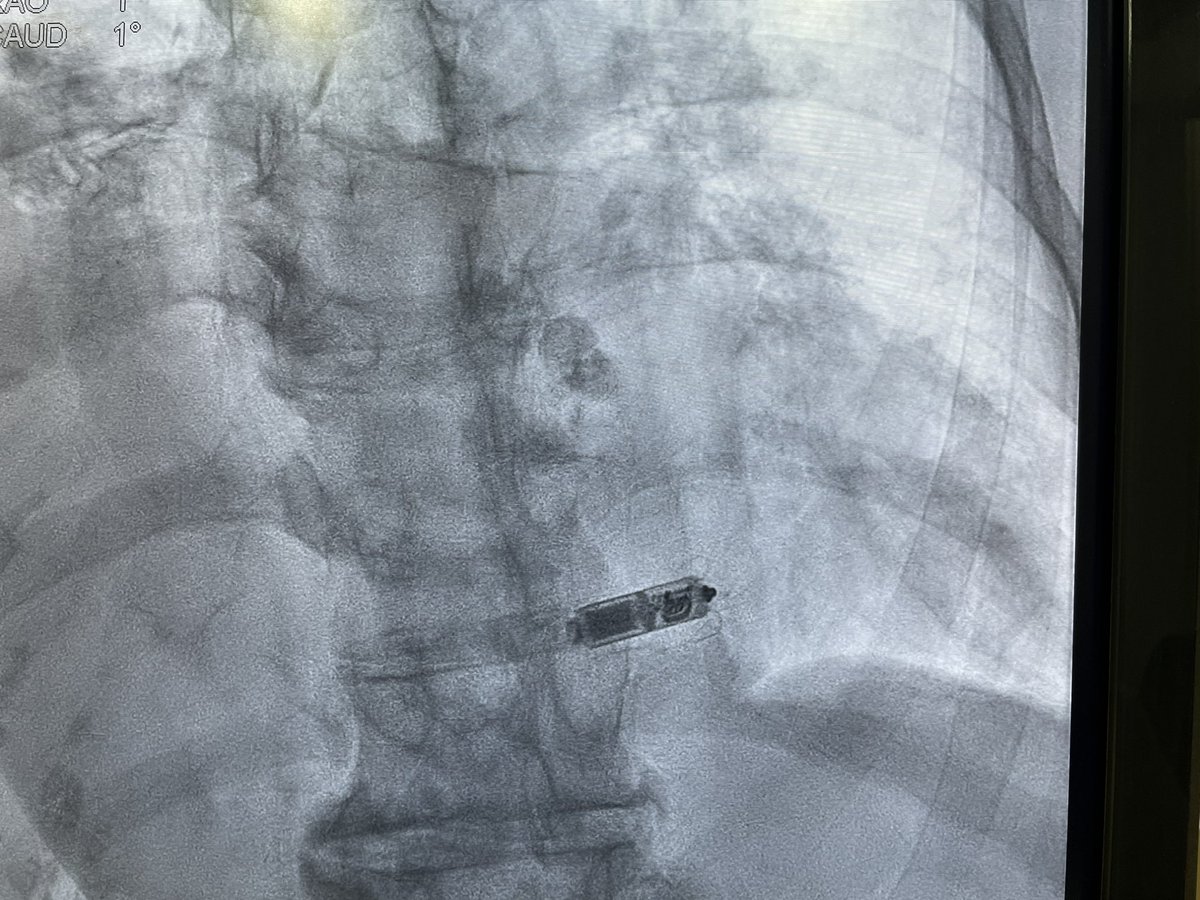

Dual chamber Leadless AVEIR pacemaker at Apollo Chennai - first in Tamilnadu and Apollo Group. - innovative, revolutionary, minimally invasive solution that ensures faster recovery and lasting comfort with physiological pacing. @Pacemaker @Apollo_Chennai @AbbottNews